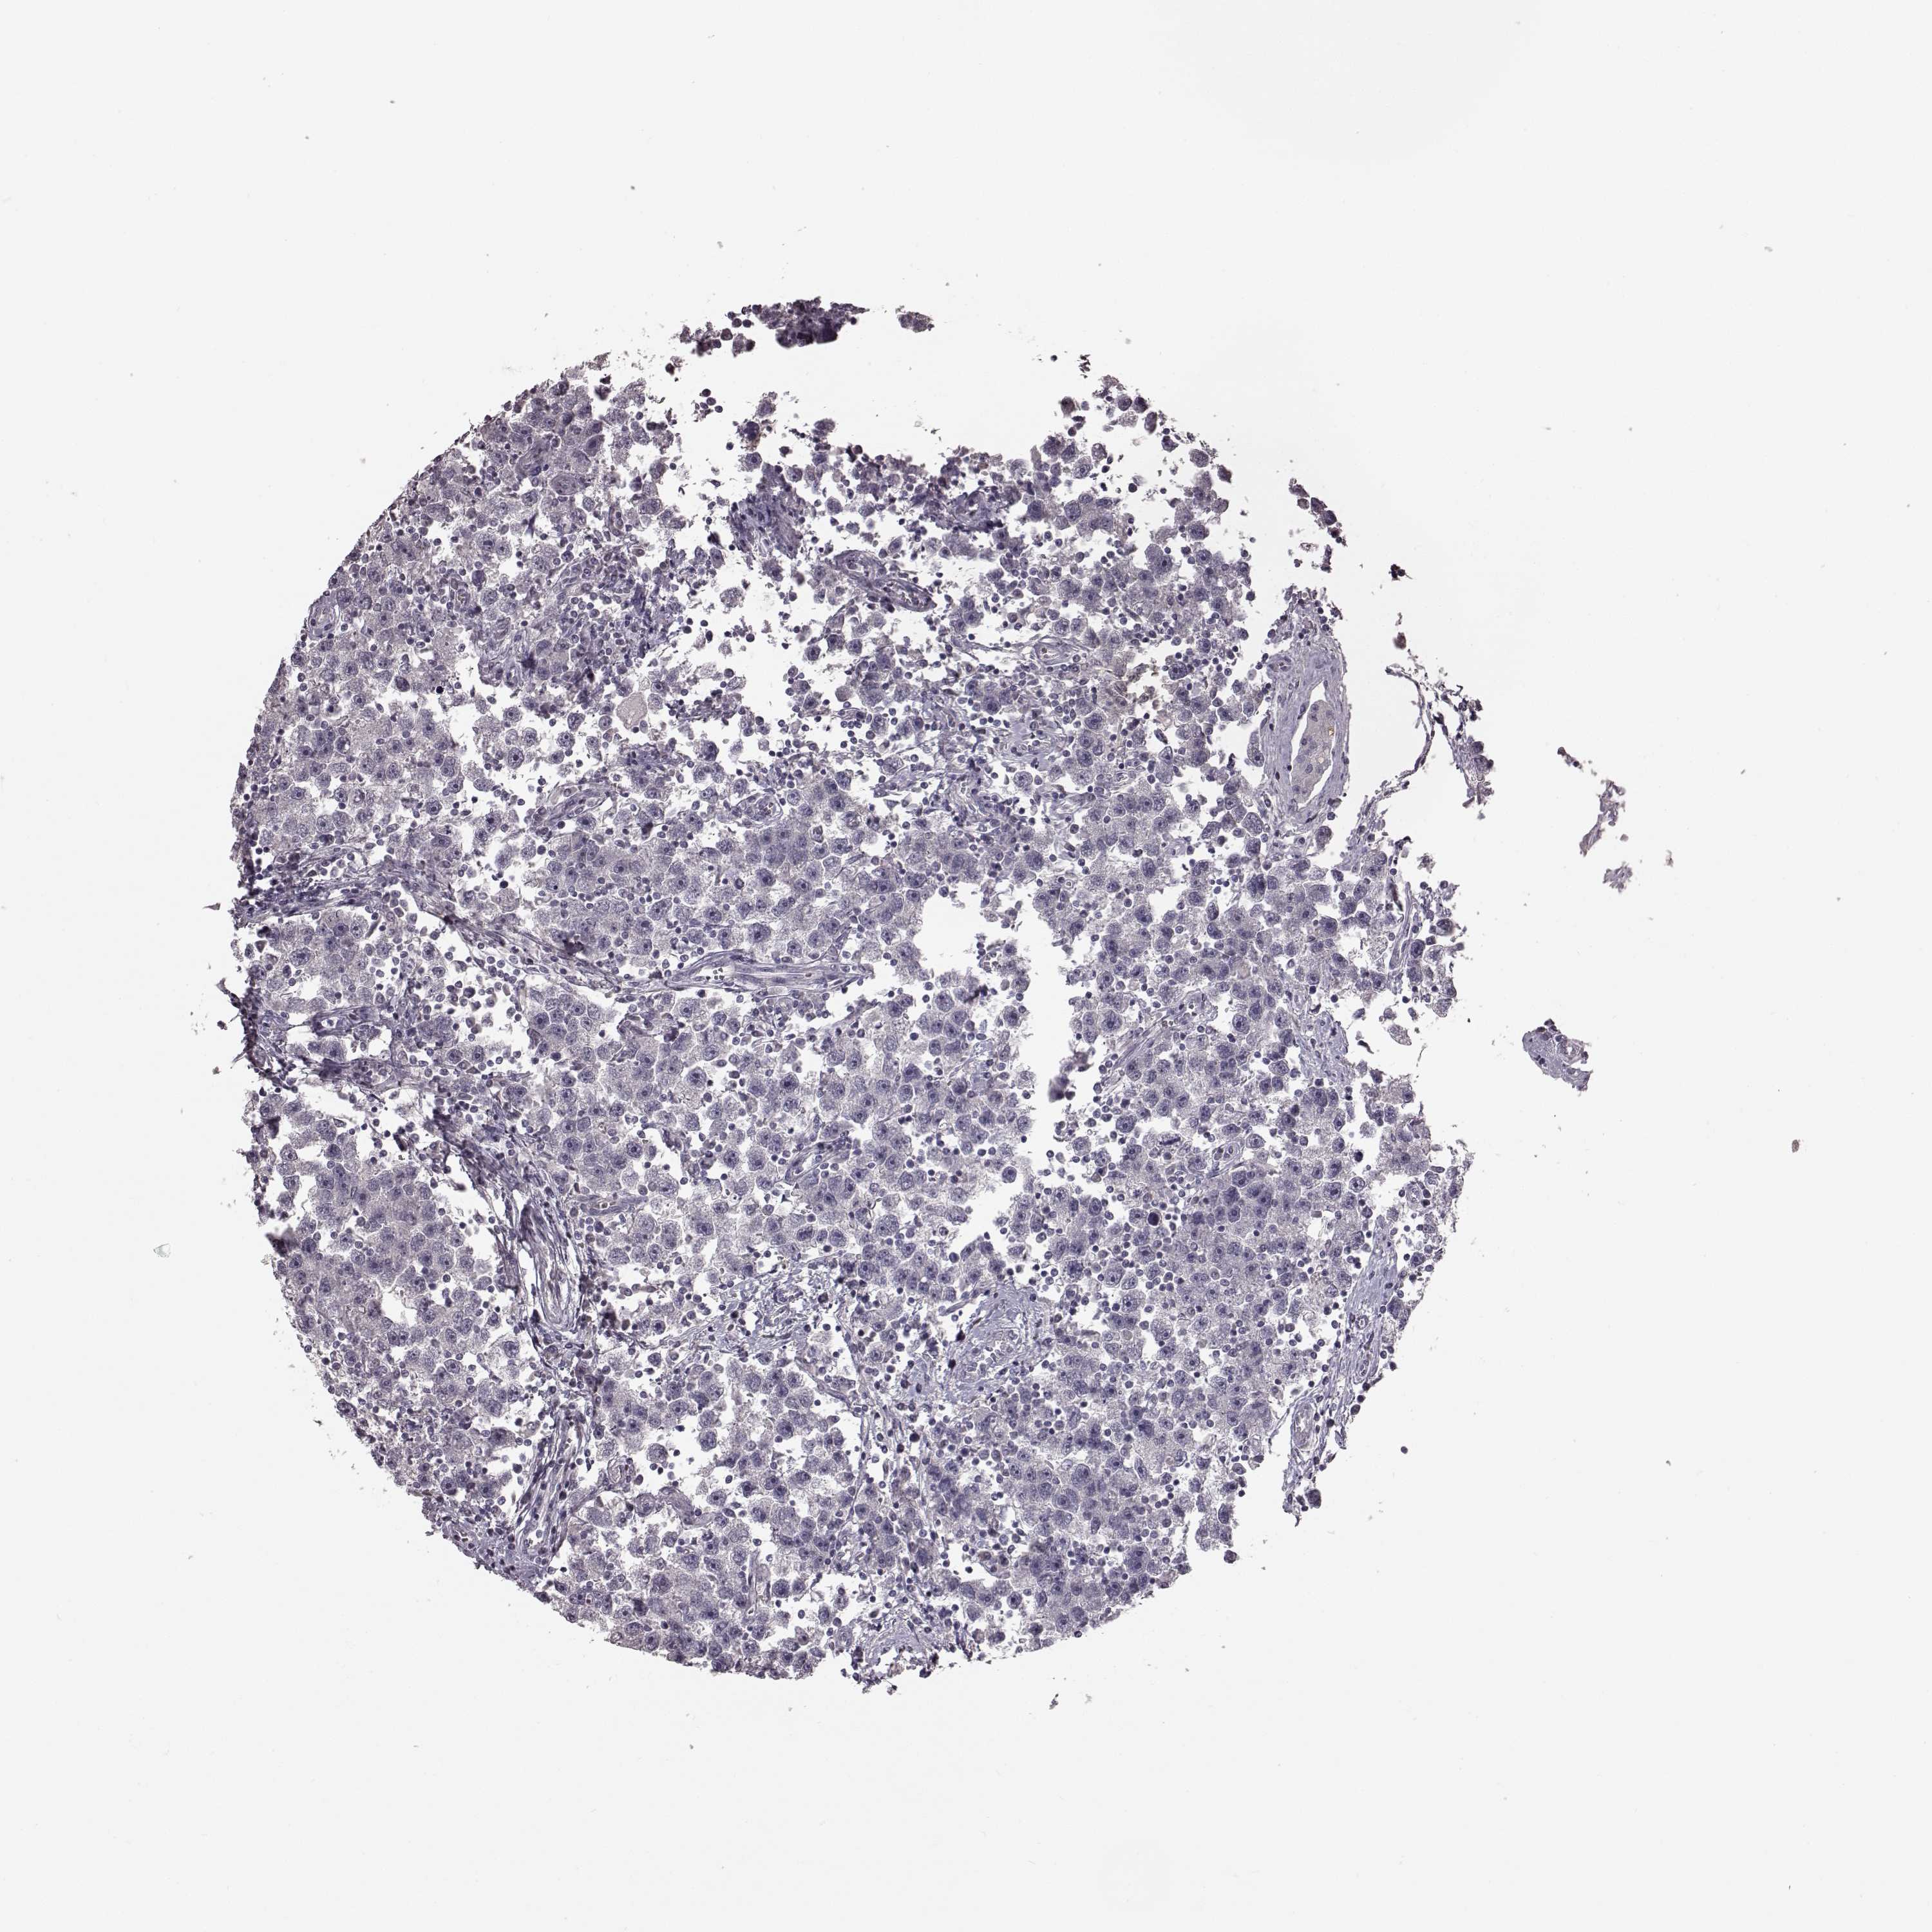

TESTIS CANCER - Protein expressioni

A mouse-over function shows sample information and annotation data. Click on an image to view it in a full screen mode. Samples can be filtered based on level of antibody staining by selecting one or several of the following categories: high, medium, low and not detected. The assay and annotation is described here.

Note that samples used for immunohistochemistry by the Human Protein Atlas do not correspond to samples in the TCGA dataset.

Antibody stainingi

Antibody staining in the annotated cell types in the current human tissue is reported as not detected, low, medium, or high, based on conventional immunohistochemistry profiling in selected tissues. This score is based on the combination of the staining intensity and fraction of stained cells.

Each image is clickable and will lead to virtual microscopy that enables deeper exploration of all samples and also displays staining intensity scores, fraction scores and subcellular localization as well as patient and tissue information for each sample.

Antibody HPA042369

Staining

High

Medium

Low

Not detected

Intensity

Strong

Moderate

Weak

Negative

Quantity

>75%

75%-25%

<25%

None

Location

Nuclear

Cytoplasmic/membranous

Cytoplasmic/membranous,nuclear

Seminoma, NOS

Carcinoma, Embryonal, NOS

Teratoma, malignant, NOS